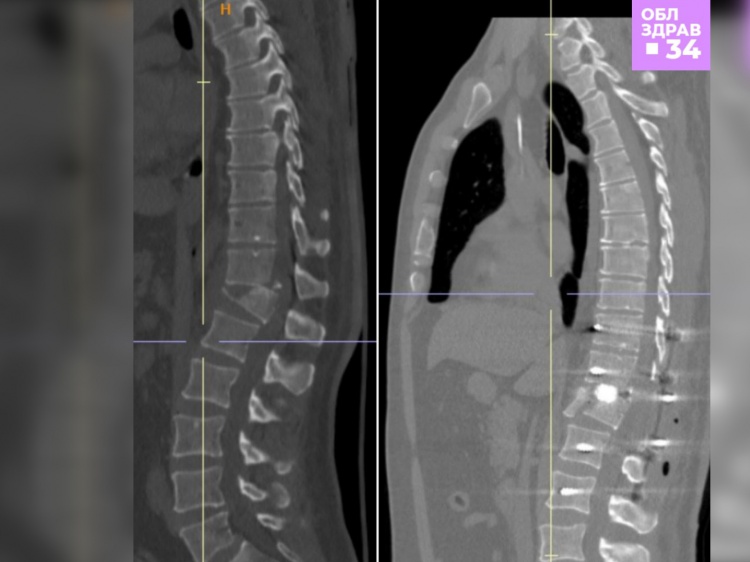

Как рассказали Волжский.ру в комитете здравоохранения, мужчина поступил в медучреждение после падения с высоты 4 этажа из-за того, что оборвались промышленные стропы. В результате у него диагностировали производственную кататравму: нестабильный осложнённый компрессионно-оскольчатый перелом позвонка, открытый перелом нижней трети костей левой голени со смещением, тупую травму грудной клетки, закрытый перелом ребер. Специалисты регионального нейрохирургического центра ВОКБ №1 в срочном порядке освободили от осколков поломанный позвонок, установили специальный имплант, который будет брать на себя опорную функцию позвоночника, пока перелом тела позвонка срастается. Также врачи установили титановые винты в тела позвонков для создания дополнительной опоры на время консолидации переломов. Одновременно с этим врачи-травматологи наложили аппарат внеочагового остеосинтеза на кости левой голени для их скорейшего срастания.

После операции у больного улучшилась чувствительность в ногах, он уже начал присаживаться в кровати. В настоящее время проходит курс раннего восстановительного лечения и ЛФК.